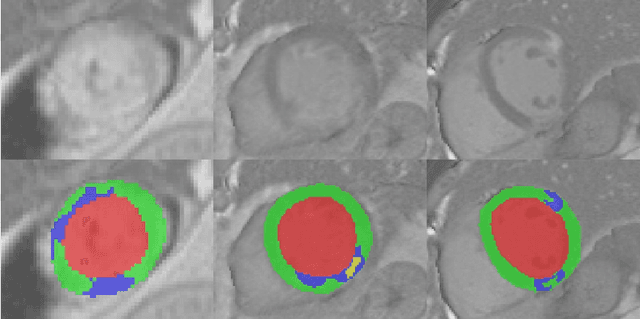

Automatic evaluation of myocardium and pathology plays an important role in the quantitative analysis of patients suffering from myocardial infarction. In this paper, we present a cascaded convolutional neural network framework for myocardial infarction segmentation and classification in delayed-enhancement cardiac MRI. Specifically, we first use a 2D U-Net to segment the whole heart, including the left ventricle and the myocardium. Then, we crop the whole heart as a region of interest (ROI). Finally, a new 2D U-Net is used to segment the infraction and no-reflow areas in the whole heart ROI. The segmentation method can be applied to the classification task where the segmentation results with the infraction or no-reflow areas are classified as pathological cases. Our method took second place in the MICCAI 2020 EMIDEC segmentation task with Dice scores of 86.28%, 62.24%, and 77.76% for myocardium, infraction, and no-reflow areas, respectively, and first place in the classification task with an accuracy of 92%.